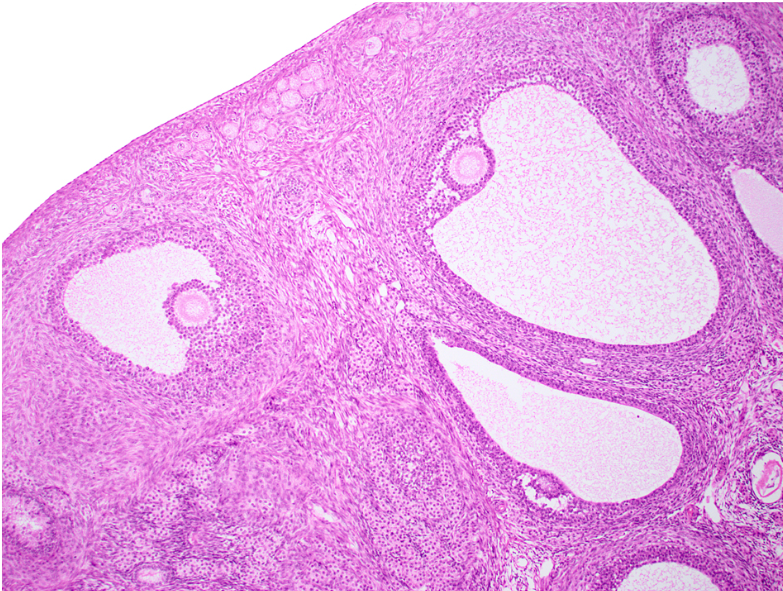

ovary (sagittal section)

antrum

corona radiata

zona pellucida

oocyte